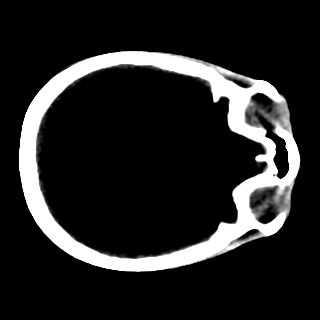

Cone-beam CT (CBCT) employs a flat-panel detector to achieve three-dimensional imaging with high spatial resolution. However, CBCT is susceptible to scatter during data acquisition, which introduces CT value bias and reduced tissue contrast in the reconstructed images, ultimately degrading diagnostic accuracy. To address this issue, we propose a deep learning-based scatter artifact correction method inspired by physical prior knowledge. Leveraging the fact that the observed point scatter probability density distribution exhibits rotational symmetry in the projection domain. The method uses Gaussian Radial Basis Functions (RBF) to model the point scatter function and embeds it into the Kolmogorov-Arnold Networks (KAN) layer, which provides efficient nonlinear mapping capabilities for learning high-dimensional scatter features. By incorporating the physical characteristics of the scattered photon distribution together with the complex function mapping capacity of KAN, the model improves its ability to accurately represent scatter. The effectiveness of the method is validated through both synthetic and real-scan experiments. Experimental results show that the model can effectively correct the scatter artifacts in the reconstructed images and is superior to the current methods in terms of quantitative metrics.